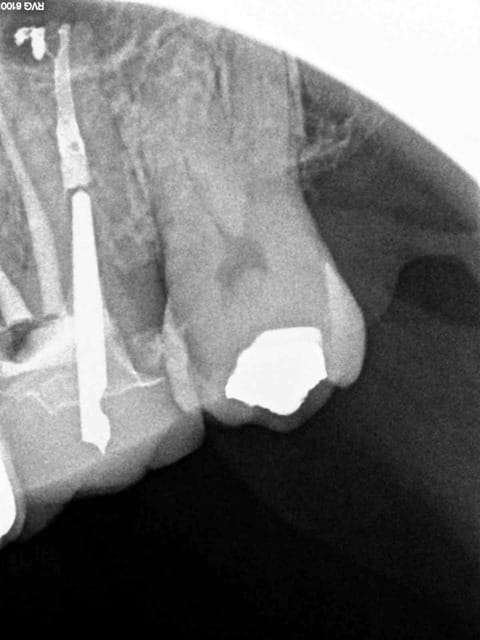

bon attend je vais chercher mes lunettes ,par ce que je ne vois rien de si mediocre au niveau endo . de quelle radio parles tu ? on parle bien de la 2 eme au milieu ?

La plus claire pour moi est la troisième tout à droite, la gutta ne disparaissant pas j'en déduis que l'obturaton sur la deuxième est constituée essentiellement, sinon exclusivement de ciment, je te fais la même en 10 minutes, tire nerfs lentulo pâte, un cône accessoire histoire de en distal.

Je suppose aussi qu'il s'agit de la radio preop du dentiste suivant et qu'il n'a pas encore déposé.

C'est quand-même dommage d'arriver à l'apex et d'obturer avec un matériau résorbable, non? Objectivement cette endo à trois ans est pourrie. La post-op ok il y a du matériau radio opaque à l'apex, mais celle avec la couronne... J'ai le souvenir d'un étudiant qui à la fac fabriquait le ciment d'obturation en mettant de l'eau distillée au lieu de l'eugénol. Pas cool.

question con surement mais en distal il y a avait un cone de gutta

il est passé ou sur l'image N°3

ca disparait pas ce genre de truc....normalement